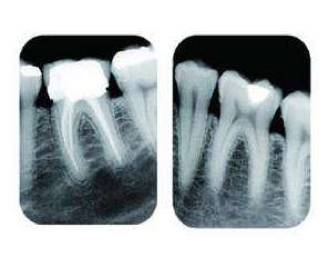

• 比如当牙齿有深部龋坏时,仅凭口内检查无法得知龋洞的深度、离牙神经的距离以及有没有并发牙根发炎等重要信息。

由于牙齿下部隐藏在牙槽骨中,口腔医生要了解牙齿的整体情况就需要拍摄全景片;要了解个别牙根及周围变化,则选择拍摄小牙片。

所以,拍牙片是一种帮助齿科医生进行诊断、治疗、疗效评估的重要手段,治疗前用于发现病变程度、范围;治疗中用于引导治疗、确定治疗范围和深度;治疗后用于观察疗效。